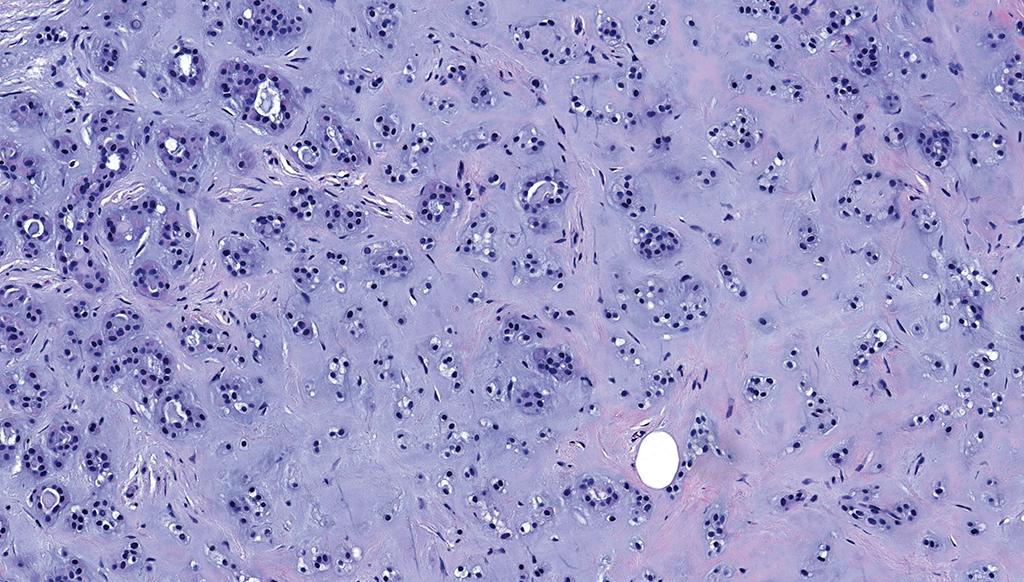

Not every epithelial tumor with papillary structures on the digit is an adenocarcinoma 🤔

Immunohistochemistry can help establish the diagnosis of hidradenoma with papillary structures.

doi: 10.1097/DAD.0000000000002291

by @JCandidoXavier

#ISDPDenver2026 #Path #pathology